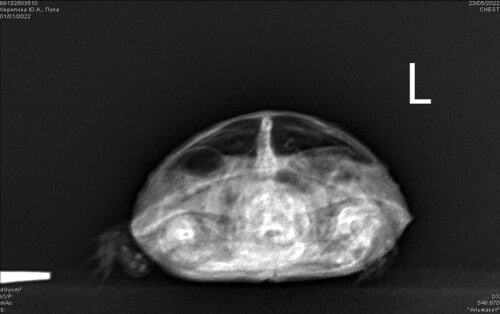

@Алла55 запишитесь на рентген на самое раннее куда сможете, нужны будут 3 проекции

image.png.9b4889a65fe34d3e5f048cf1b94d3b13.pngimage.png.1ad376f4bf1b7a663093be68542df126.pngimage.png.a36fbe8912080fbf5cdc2e9d88c2ca9e.png

Но вот какой антибиотик уже будет решать врач, если там действительно пневмония. Но я сразу предупрежу, что у таких черепах прогнозы очень осторожные, т.к. такие состояния наступают когда уже всё, организм полностью истощён и зачастую лечить что-то уже поздно. Но попытаться стоит.